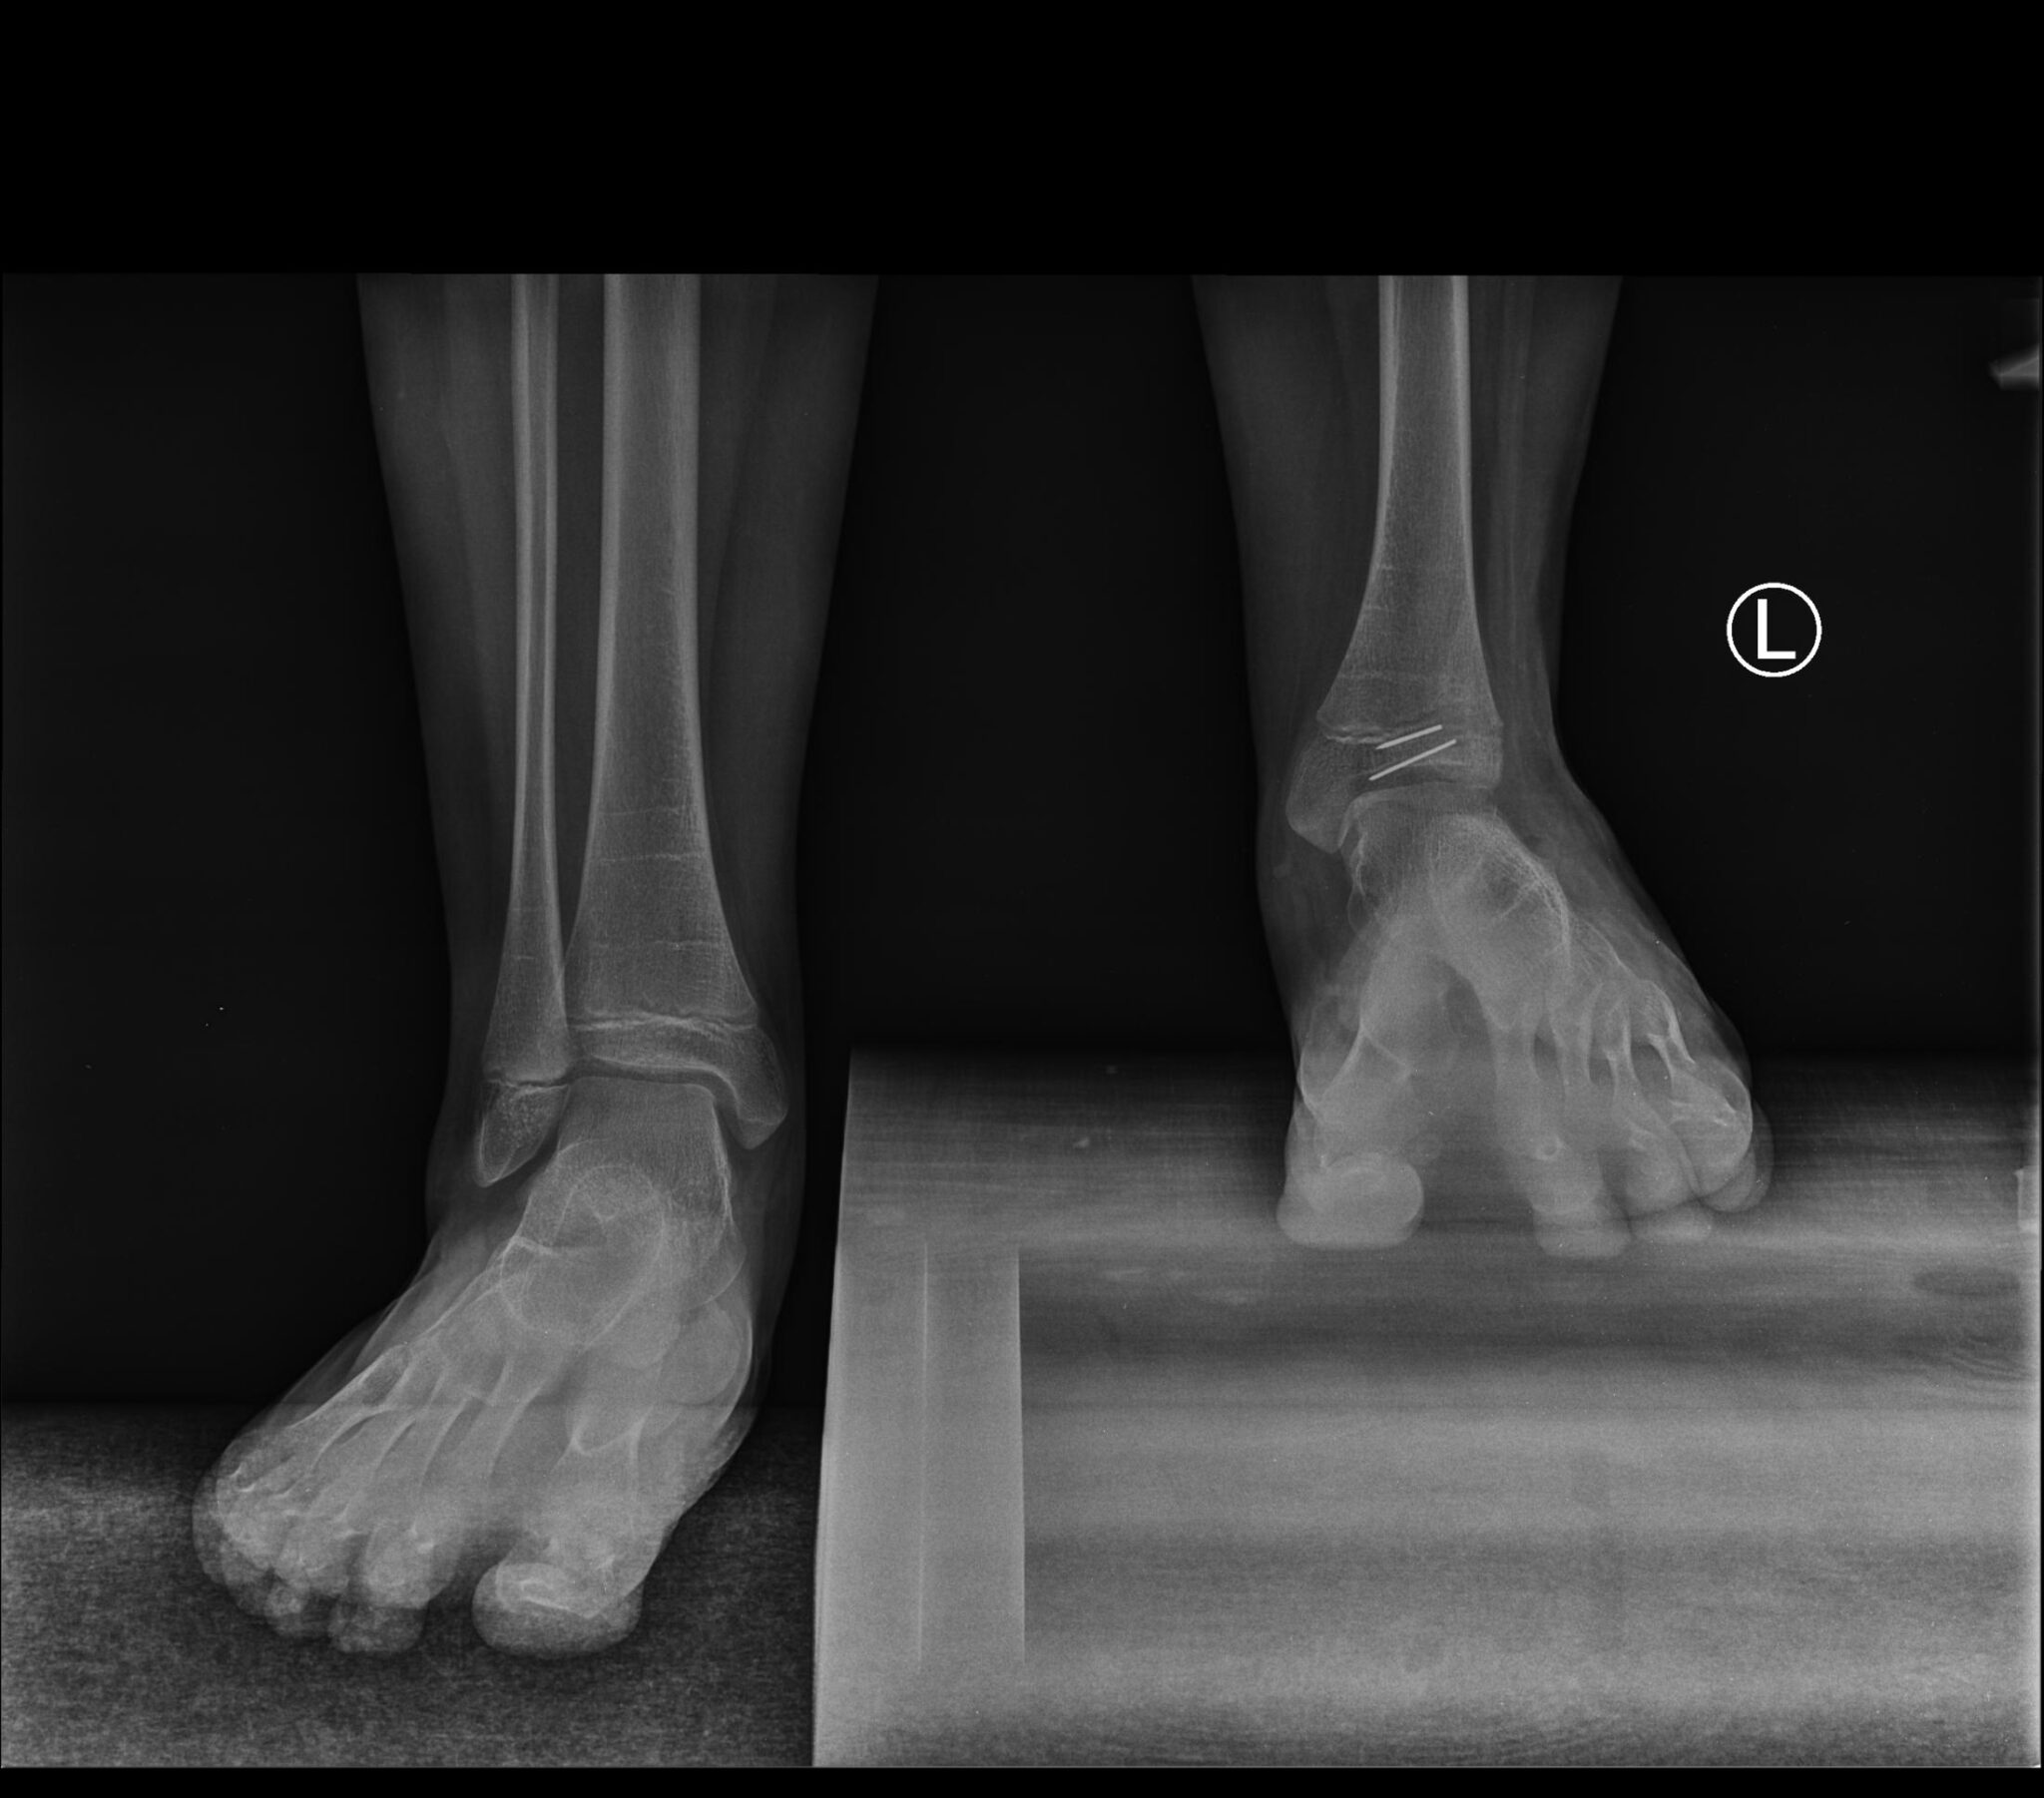

Nasz syn Mateusz urodził się 23 sierpnia 2009 roku jako zdrowy chłopiec. Po porodzie, ani wcześniej w czasie ciąży, nic nie wskazywało na późniejsze problemy zdrowotne. Jednak gdy synek zaczął stawać – robił to na paluszkach lewej nogi. Po wykonanych badaniach RTG okazało się, że Mateusz nie ma kości strzałkowej lewej, skrócenie piszczeli oraz kości udowej.

Postanowiliśmy szukać pomocy u innych lekarzy. W 2018 roku trafiliśmy do Paley Institute w Warszawie, gdzie po badaniu okazało się, że Mateusz ma lewą nogę krótszą od prawej o 5 centymetrów. 25 kwietnia 2019 roku syn przeszedł pierwszą udaną operację, której koszt pokryliśmy ze środków własnych, a która miała na celu przygotowanie nogi syna do wydłużenia.